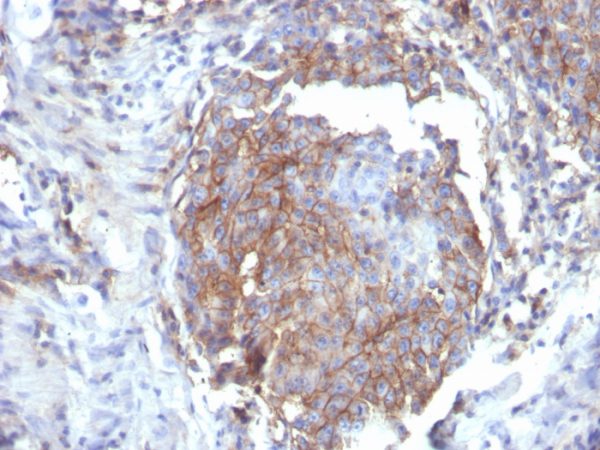

Formalin-fixed, paraffin-embedded human breast stained with CD44 Recombinant Mouse Monoclonal Antibody (rHCAM/6449).